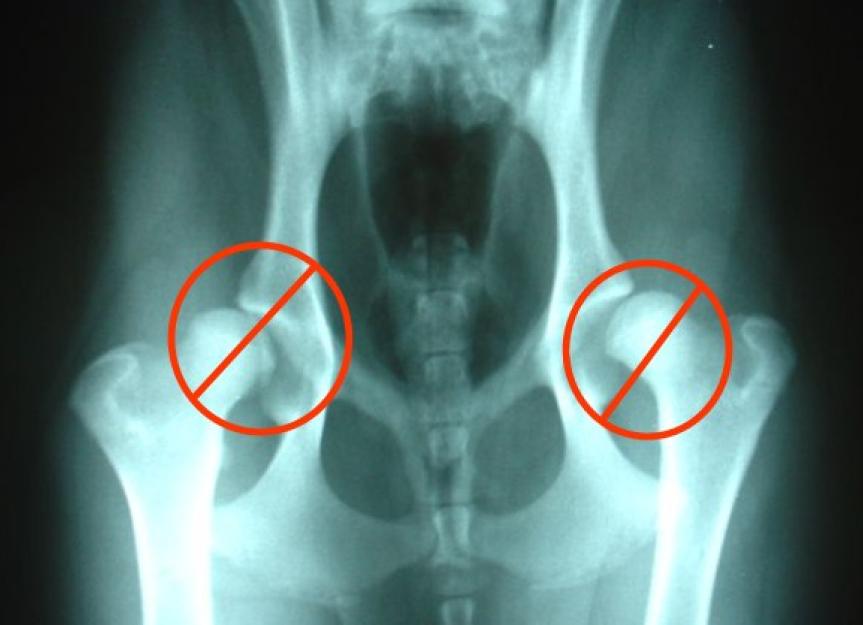

How To Help a Dog With Hip Dysplasia (13 Different Ways) Dog hip